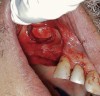

The lateral approach is also used for sinus floor elevation. It is indicated when there is reduced residual bone height, which does not allow standard implant placement or placement of implants in combination with minor sinus floor elevation using the osteotome technique (Figure 1, Figure 2 and Figure 3). Contraindications are excessive interarch distance due to unfavorable crown-to-root ratio, acute or chronic unresolved sinusitis, current sinus pathology (eg, cysts or tumors), lodged root tips in the sinus, history of heavy smoking, a systemic compromise, and psychological problems.

Figure  1  Elevation of the flap.

Figure 1

Figure  2  Outline of the lateral window

Figure 2

Figure  3   Elevation of the bony window.

Figure 3